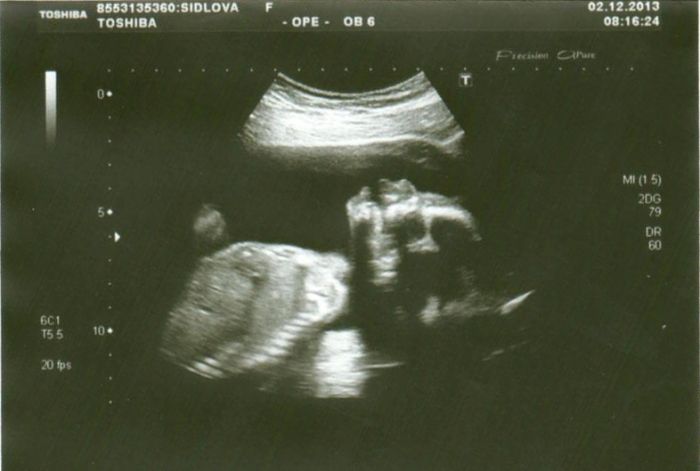

Autor: shidlinka 23.12.2013 v 09:03